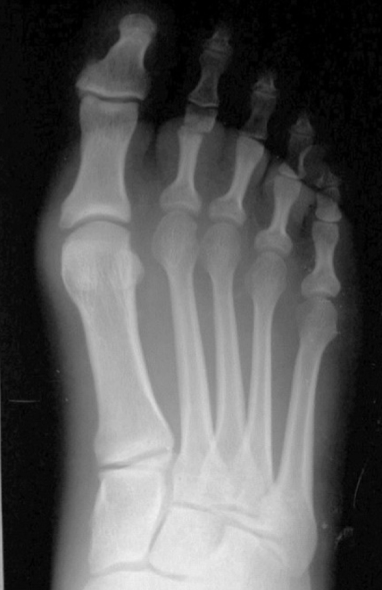

Stress Fracture

Stress fracture –

gradually develops

from multiple

repetitions of force